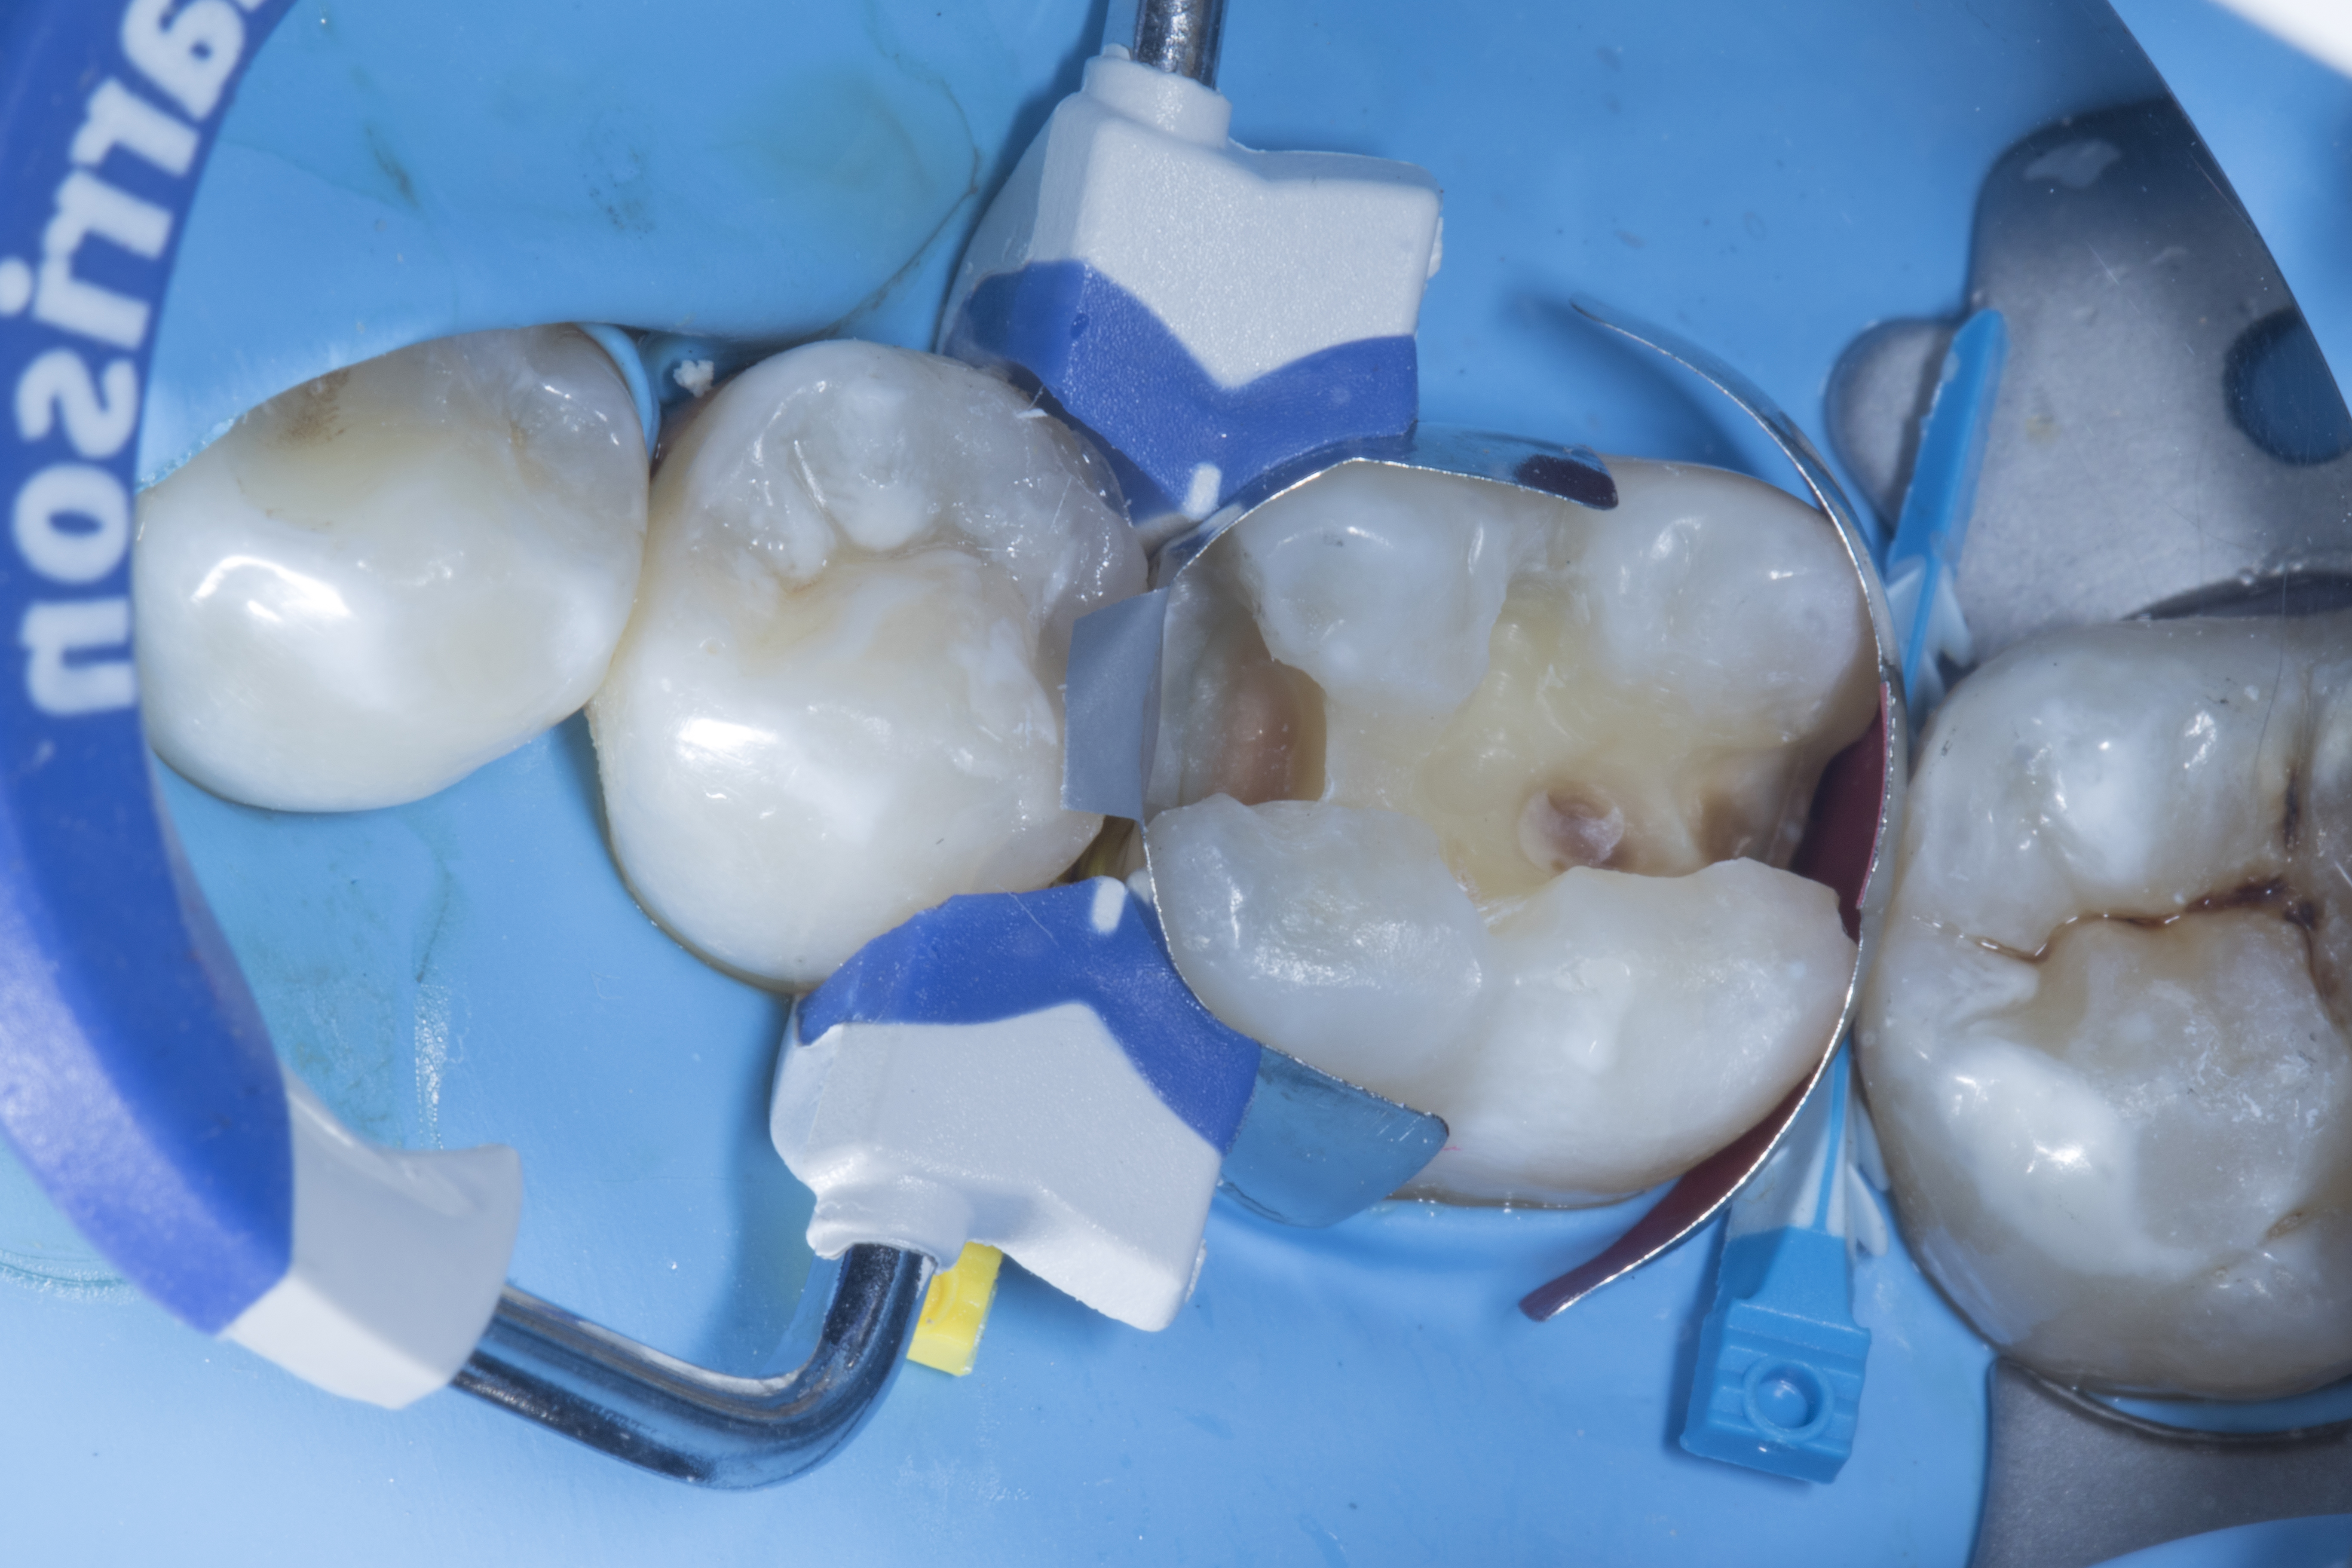

Figure 1

Figure 1. A carious lesion on tooth #35 distally and #36 both mesially and distally. Tooth #36 shows old composite restoration.

Step 1 - Rubber dam isolation was done with a heavy dam. This is important if you want to achieve optimal bonding to increase longevity of the restoration.

Step 2 – Restoration of tooth #35. After the initial cavity preparation, a deeper carious lesion was identified. Caries dye was applied to effectively remove caries with the help of a slow speed round carbide bur.

Figure 2

Figure 2. After the initial cavity preparation a deeper carious lesion was identified.